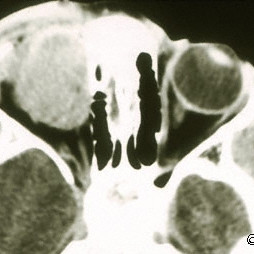

Sclerosing pseudotumor

Sclerosing pseudotumor - CT coronal image - nasal orbit- Note the irregular tumor margins.